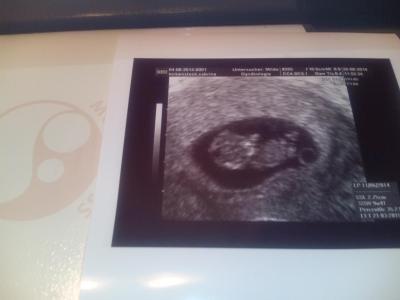

40 min blut gesucht schon wieder und 5 mal gestochen alle arme total blau Dem kleinen Wunder geht es gut es ist Zeit gerecht entwickelt nur darf noch mehr Tabletten schlucken Und hab erst in drei Wochen einen Termin noch so lang Anbei ein foto

Bild zu fa termin un mutterpass - Forum für März - Mamis

Tolles Foto ;) Schon so gross :) Das mit dem Blut ist ja Mist, aber wir wissen ja wofür wir das tun! Freut mich das alles gut ist! LG

Wow, so schön groß schon